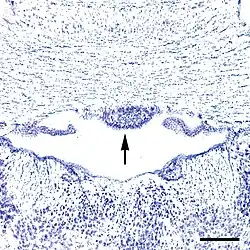

Como se señaló anteriormente, los capilares en algunas subregiones dentro del SFO están fenestrados,[6] de manera que carecen de una barrera hematoencefálica. Con la excepción del órgano subcomisural, todos los demás órganos circunventriculares contienen capilares fenestrados,[2] característica que los distingue de la mayoría de las demás partes del cerebro.[7] El SFO puede dividirse en seis zonas anatómicas de acuerdo con su topografía capilar, dos en el plano coronal y cuatro en el plano sagital.[3] La zona central está compuesta por las células gliales y cuerpos celulares neuronales, así como una alta densidad de capilares fenestrados.[8] Las áreas rostral y caudal tienen, por su parte, una menor densidad de capilares[8] y están compuestas principalmente de fibras nerviosas, encontrándose menos neuronas y células gliales en esta área. Con todo, desde el punto de vista funcional, el SFO puede dividirse en dos porciones: la división periférica dorsolateral y el segmento central ventromedial.[9]